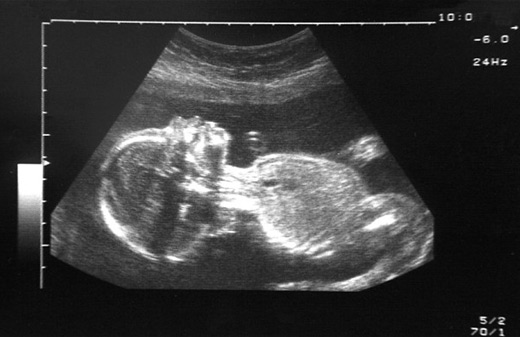

The mother was fed with special nutrient-rich fluids while a battery of sensors monitored the status of the child. “For three months we managed to keep the baby alive, and then it was delivered on the 27th week with a caesarean section,” Prof Fulesdi said. “The baby is now home and growing.”